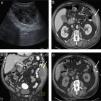

A) EcografÃa abdominal: colección 4,2×9,1×10,3cm. B) TC abdominal con contraste iv y rectal (corte axial), colección hipodensa con realce periférico situada en la pared abdominal lateral (flecha blanca). C) TC abdominal con contraste iv y rectal (corte sagital), la colección descrita en B (flecha blanca), sin fuga de contraste rectal. D) Drenaje radiológico guiado por TC en el espesor de la colección.

Varón de 73 años al que se realizó colonoscopia donde se extirparon, con asa diatermia, 2 pólipos en colon ascendente de 5 y 6mm, uno en colon transverso de 5mm, y otros 2 a 40cm y 30cm de margen anal, de 12mm y 9mm, respectivamente (todos «Is» según la clasificación de Paris). Todos ellos fueron esclerosados con adrenalina (diluida al 1:10.000 en suero fisiológico), y se aplicaron clips en las escaras de los pólipos de mayor tamaño (12 y 9mm), quedando las heridas visualmente bien selladas. Dos semanas más tarde, el paciente consultó en urgencias por dolor en flanco izquierdo y fiebre. A la exploración se apreció tumoración de la pared abdominal a ese nivel, con celulitis y fluctuación asociada, con el resto de la exploración abdominal anodina. Una ecografÃa objetivó una colección de hematoma de 4,2×9,1×10,3cm en el espesor del músculo transverso abdominal (fig. 1A). Se solicitó TC abdominal con contrate intravenoso y rectal (figs. 1B y C), que mostró una colección hipodensa con realce periférico situada en la pared abdominal lateral izquierda, que rechazaba medialmente al peritoneo parietal. Contactaba Ãntimamente con el colon descendente proximal al que desplazaba, sin identificar una comunicación con el mismo o fuga de contraste desde el colon a la colección. Se drenó la colección con catéter radiológico guiado por TC, donde se obtuvo material achocolatado purulento maloliente cuyo cultivo aisló Escherichia coli, Klebsiella oxytoca y Proteus mirabilis. El paciente ingresó en planta de cirugÃa con piperacilina-tazobactam como antibiótico intravenoso empÃrico. La evolución fue favorable, desapareciendo la fiebre y los signos externos de infección. En todo momento fueron correctos el tránsito digestivo y la tolerancia oral. Se retiró el drenaje por escaso debito previo control radiológico (fig. 1D) y fue dado de alta al 6.° dÃa.